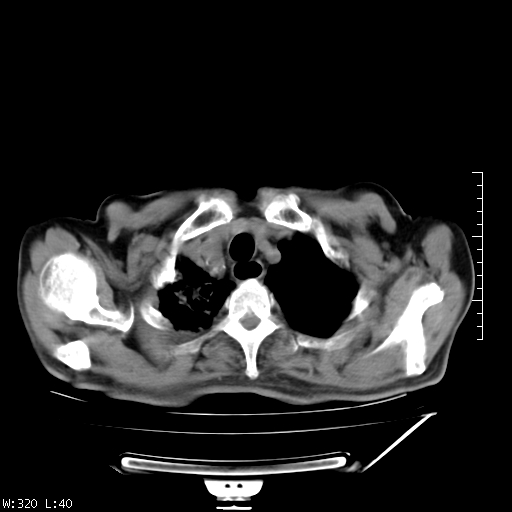

标题: CT23994:男、72、咳嗽、气短两月余,近来消瘦。 [打印本页]

标题: CT23994:男、72、咳嗽、气短两月余,近来消瘦。

右上肺实变,与胸膜关系密切,右肺容积缩小,隆突下淋巴结增大,考虑1 肺结核 2 肺癌

右上肺大片状密度增高影,与胸膜关系密切,内见低密度透亮影,胸膜下可见三角形不张影,左下肺沿支气管走形结节影,纵膈内淋巴结显示。考虑结核并疤痕性不张可能性大,建议穿刺活检,排除肺泡癌。